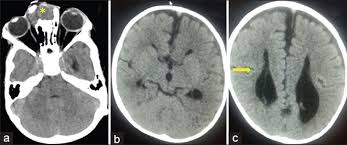

After birth, an MRI is commonly used to obtain detailed images of the brain and skull. This can help determine the size and location of the encephalocele, as well as assess any associated brain tissue involvement or damage.

3. CT Scan

A CT scan may be used to get a clearer picture of the encephalocele and any related bone deformities. It is also helpful in planning surgical treatment.